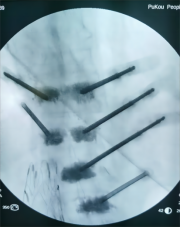

8. 机器人导航辅助下脊柱侧弯矫正技术

脊柱侧弯是一种复杂的脊柱三维畸形,其中以青少年特发性脊柱侧凸最常见。我院在浦口地区率先开展机器人导航辅助下脊柱侧弯矫正术,实现了脊柱侧弯手术准确、微创、智能化的突破,获得了良好的效果。还有老年人退变性侧弯,机器人亦可精准置入困难椎弓根螺钉,误差只有0.3mm。